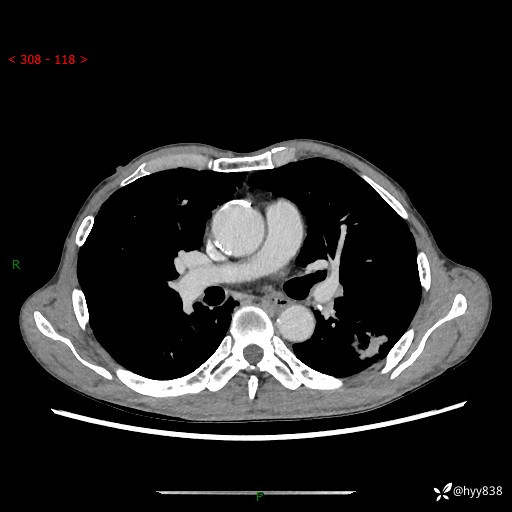

现病史:患者于1月余前无明显诱因出现背部疼痛不适,无明显咳嗽、咳痰、胸闷、咯血、发热等不适,后于2024.5.3至当地市人民医院行胸部CT示:左肺下叶结块,大小约2.2cm*2.6cm,双肺多发小结节,双肺感染性病变,部分纤维增值灶,慢支并双肺局限性肺气肿,肺大泡,纵隔淋巴结增大并部分钙化,冠脉区及大血管壁钙化,双侧胸膜局限性增厚;后口服莫西沙星2周。2024.6.12复查胸部CT示:左肺下叶结块影形态较前饱满,较大截面范围约2.8cm*2.3cm,边缘可见细短毛刺及分叶,性质待查。现患者为求进一步诊治来我院,门诊以“肺占位”收入我科。 起病来,患者精神、食欲、睡眠尚可,大小便正常,体力体重轻微下降。

胸部CT平扫+增强

各期CT值:48hu 100hu 78hu